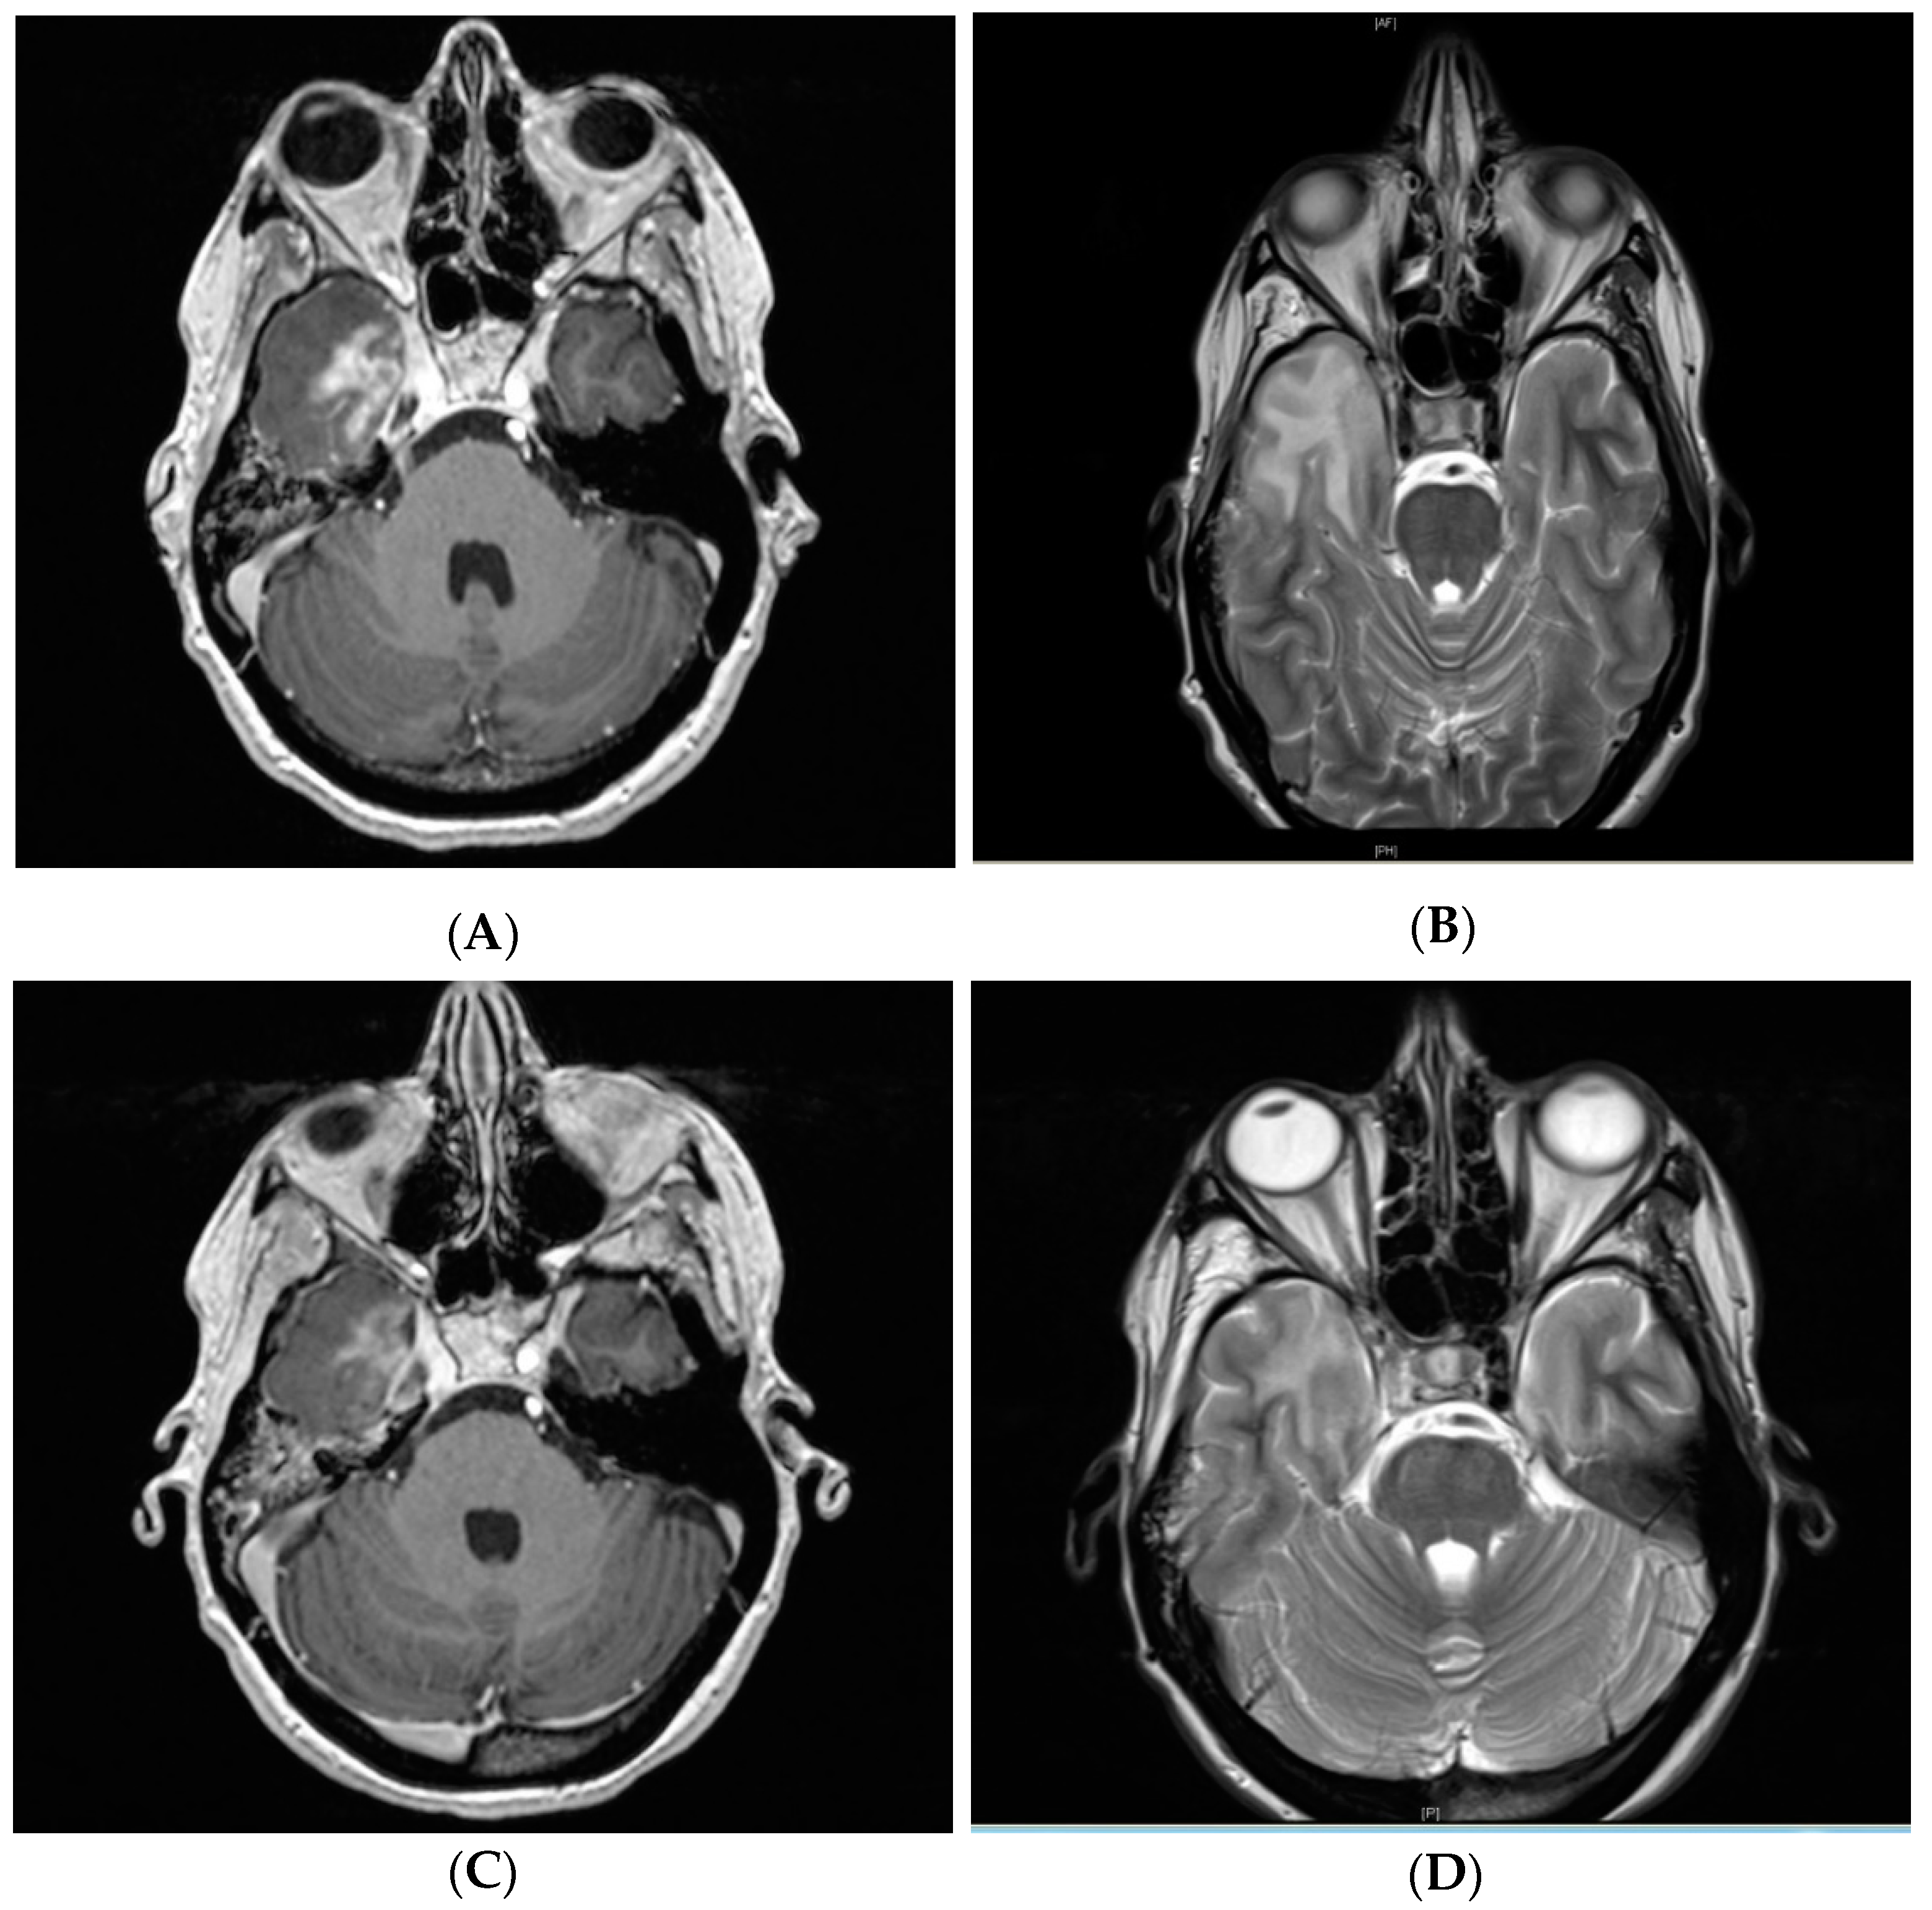

Figure 3.

T1-weighted contrast-enhancement (A) and T2 alteration (B) post-treatment follow-up MR imaging of the same patient from Figure 2 showing grade III symptomatic CNSN in the right temporal lobe 11.9 months after treatment. Radiographic response after intravenous bevacizumab 7.5 mg/kg administered at two-week intervals for four treatments with residual T1-weighted contrast-enhancement (C) and T2 hyperintensity (D). The patient also responded clinically with swift recovery from double vision, vertigo, and headaches.